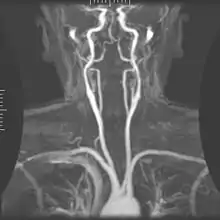

Angiography

Magnetic resonance angiography (MRA) generates pictures of the arteries to evaluate them for stenosis (abnormal narrowing) or aneurysms (vessel wall dilatations, at risk of rupture). MRA is often used to evaluate the arteries of the neck and brain, the thoracic and abdominal aorta, the renal arteries, and the legs (called a "run-off"). A variety of techniques can be used to generate the pictures, such as administration of a paramagnetic contrast agent (gadolinium) or using a technique known as "flow-related enhancement" (e.g., 2D and 3D time-of-flight sequences), where most of the signal on an image is due to blood that recently moved into that plane (see also FLASH MRI).[47]

Techniques involving phase accumulation (known as phase contrast angiography) can also be used to generate flow velocity maps easily and accurately. Magnetic resonance venography (MRV) is a similar procedure that is used to image veins. In this method, the tissue is now excited inferiorly, while the signal is gathered in the plane immediately superior to the excitation plane—thus imaging the venous blood that recently moved from the excited plane.[48]